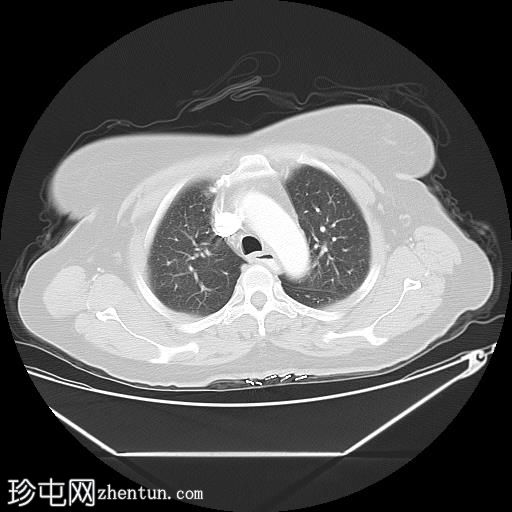

轴位

肺

中段食管壁增厚,提示

肿瘤

浸润,长约10厘米。肿块与左主支气管后壁及降主动脉紧密接触。未见侵犯邻近结构的迹象,也未触及区域淋巴结肿大。